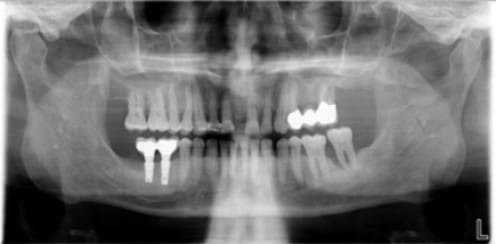

Non Annie, l'implant ne rentre pas dans la racine de 25. L'espace est étroit, mais l'implant est bien centré (voir Rx jointe).

En ce qui concerne les antagonistes, la 37 est + solide qu'il n'y parait à la Rx malgré une petite perte osseuse mésiale. J'ai réalisé un bridge 35/36/37 pendant l'ostéointégration. (l'effondrement de la crête ne permettant pas la pose d’un implant/36).

Ben, ça alors, j’avais pas remarqué le gros problème en bas à droite !!

Bien sûr Marc, tu as raison, il vaut mieux assainir la bouche avant de mettre en place des implants. Mais le patient souhaitait avoir la possibilité de mastiquer du coté droit pendant l’ostéointégration à gauche. Le RV est déjà programmé pour l’extraction de ces dents juste après la pose de la prothèse sur les implants.

En ce qui concerne le cas qui n'a pas marché, l'état buccal était parfaitement sain par ailleurs, pas de problème paro!

Carole, je prendrai un pano que je posterai le jour du retrait des points. Mais je ne pense pas que ça t’informe plus par rapport à la 1ère Rx.